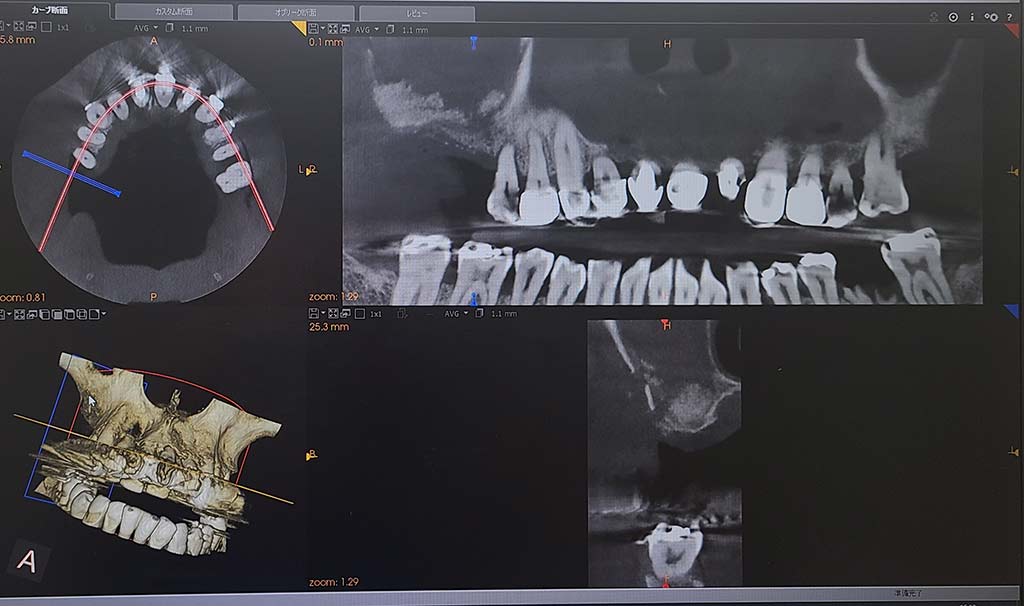

インプラント治療をするうえでまずはCTを撮影して骨があるかの確認をします

個人歯科医院ではまだまだ導入が少ないCT(コンピュータ断層撮影)でお口の中を撮影し、神経や上顎洞の位置を正確に把握し骨の状態を確認しインプラント治療計画をご提案します。 わかりやすい説明で、納得した上で安心して治療を受けていただけます。

1. CT撮影

CTとはX線を利用して体内の断面図を撮影する技術で、立体的に神経、血管、骨などの様子を把握することができます。

インプラント治療は骨がないと治療ができないため必ずCTを撮影して診断いたします。

骨の形や骨質、高さや幅には個人差があります。歯がどのように失ってしまったのかで変わってきます。

また、骨の中には神経や太い血管が通っていますので慎重に確認をしていきます。

CT撮影

2.コンピューター上で治療を計画

院内技工所でCT撮影データーから得られた情報を基に、神経や太い血管を避けながらインプラントの埋め込み位置院長とを計画します。

埋め込むインプラントのサイズや、角度、深さ等をソフトウェアでシュミレーションしますガイドを作成していきます。